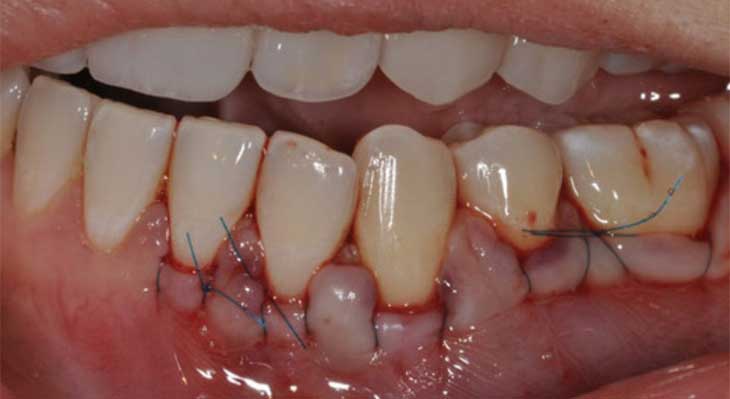

• مرحله پنجم؛ قرار دادن و بخیه زدن پیوند: بافت پیوندی با دقت در بستر آماده شده قرار داده شده و با استفاده از بخیه های بسیار ظریف در جای خود محکم میشود تا در طول دوران نقاهت ایمپلنت دندان و پیوند لثه، ثابت باقی بماند.

اگرچه تکنیک های مختلفی برای جراحی پیوند لثه وجود دارد، اما مراحل کلی اکثر آن ها مشابه است و معمولاً تحت بی حسی موضعی در مطب دندانپزشکی انجام میشود. این فرآیند با یک برنامه ریزی دقیق آغاز میشود.

• مرحله سوم؛ آماده سازی بستر گیرنده: جراح با ایجاد برش های ظریف، یک بستر مناسب را در ناحیه تحلیل رفته برای پذیرش بافت پیوندی آماده میکند. این کار ممکن است شامل کنار زدن بافت لثه موجود باشد.

• مرحله چهارم؛ برداشتن بافت پیوندی: اگر قرار است از بافت خود بیمار استفاده شود، جراح با دقت و مهارت، قطعه ای از بافت را به اندازه و ضخامت مورد نیاز از ناحیه سقف دهان برمیدارد و محل آن را بخیه یا با پانسمان مخصوص میپوشاند.